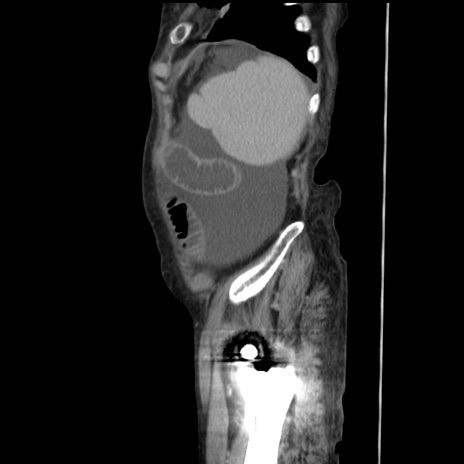

症例31(矢状断像)

【症例】80歳代 女性

【主訴】腹部膨満感

【現病歴】他院にて肝硬変にてフォロー中。1週間前から便秘、腹部膨満感、臍部腫瘤あり受診となる。

【既往歴】肝硬変

【身体所見】腹部膨隆あり、皮膚変化なし、疼痛なし。

【データ】WBC 4600、CRP 0.25